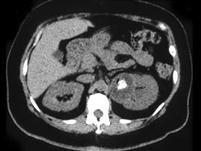

问题 女,42岁,左侧腰痛伴尿频、尿急、尿痛,尿白细胞(++),尿细菌培养为大肠杆菌,请根据所示图像,选择最可能诊断 ( )

选项 A、左侧肾转移瘤 B、左侧局限型黄色肉芽肿性肾盂肾炎 C、左侧肾结核 D、左侧肾脓肿 E、左侧肾癌

答案 B